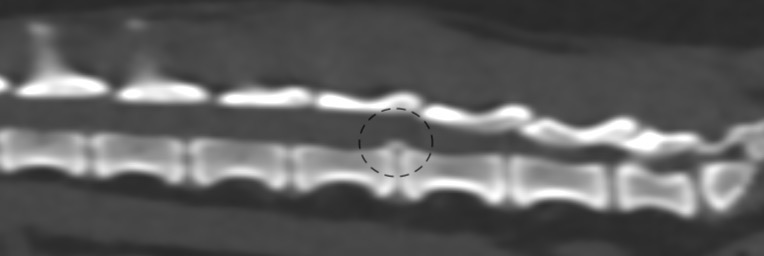

第5-6腰椎間椎間板の脊柱管への突出・石灰化が認められ、左側での脊髄の圧迫所見が認められました。*黒線で囲った部位

第3-4腰椎間椎間板の脊柱管への突出・石灰化が認められ、右側での脊髄の圧迫所見が認められました。*黒線で囲った部位

第4-5腰椎間椎間板の脊柱管への突出・石灰化が認められ、左側での脊髄の圧迫所見も認められました。*黒線で囲った部位

第7腰椎-仙椎間椎間板の脊柱管への突出・石灰化が認められ、中央での脊髄の圧迫所見が認められました。*黒線で囲った部位